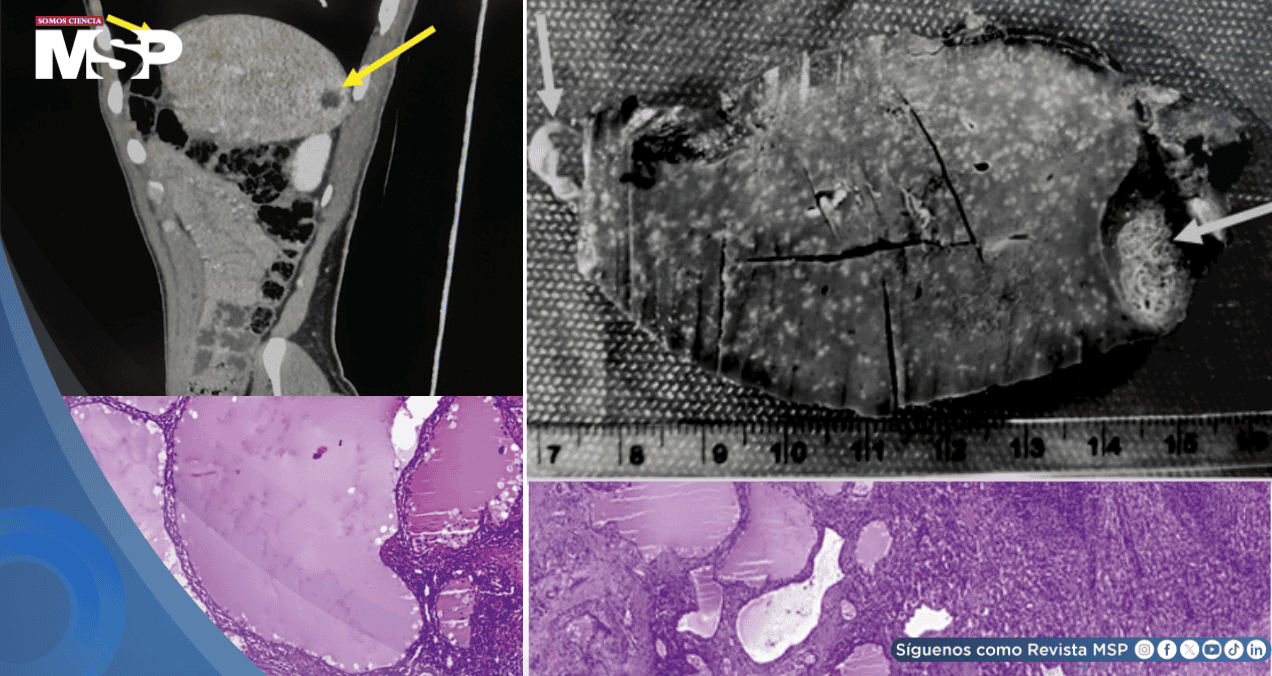

Ante la sospecha radiológica, se realizó una tomografía computarizada (TC) abdominal con contraste. Las imágenes mostraron varias lesiones quísticas en el bazo, la mayor de 24 milímetros, con un realce tenue del contraste.

El análisis patológico del bazo extirpado reveló un diagnóstico completamente diferente y benigno. Las lesiones no correspondían a linfoma, sino a un linfangioma esplénico. Macroscópicamente, se observaron quistes multiloculados llenos de líquido.

Microscópicamente, el estudio histológico confirmó la presencia de múltiples espacios quísticos irregulares revestidos por células endoteliales, típicos de este tumor benigno de los vasos linfáticos. Este hallazgo descartó por completo la recurrencia del cáncer y explicó el origen de las lesiones detectadas en las imágenes.